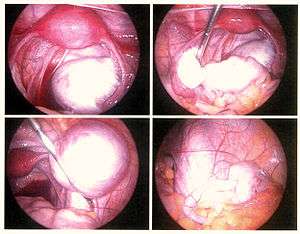

Surgery

Conservative treatment consists of the excision of the endometrium, adhesions, resection of endometriomas, and restoration of normal pelvic anatomy as much as is possible.[62] Endometrioma on the ovary of any significant size (Approx. 2 cm +) -sometimes misdiagnosed as ovarian cysts- must be removed surgically because hormonal treatment alone will not remove the full endometrioma cyst, which can progress to acute pain from the rupturing of the cyst and internal bleeding. Laparoscopy, besides being used for diagnosis, can also be used to perform surgery. It's considered a "minimally invasive" surgery because the surgeon makes very small openings (incisions) at (or around) the belly button and lower portion of the belly. A thin telescope-like instrument (the laparoscope) is placed into one incision, which allows the doctor to look for endometriosis using a small camera attached to the laparoscope. Small instruments are inserted through the incisions to remove the endometriosis tissue and adhesions. Because the incisions are very small, there will only be small scars on the skin after the procedure, and all endometriosis can be removed, and women recover from surgery quicker and have a lower risk of adhesions.[63]